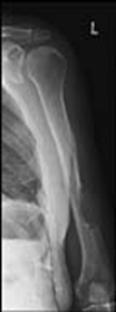

Fractura de humerus

Fracturi simple: SPIRALA OBLICA TRANSVERSALA

Fractura spirala de Fractura transversa de diafiza femurala Fractura spirala de diafiza tibiala

diafiza humerala